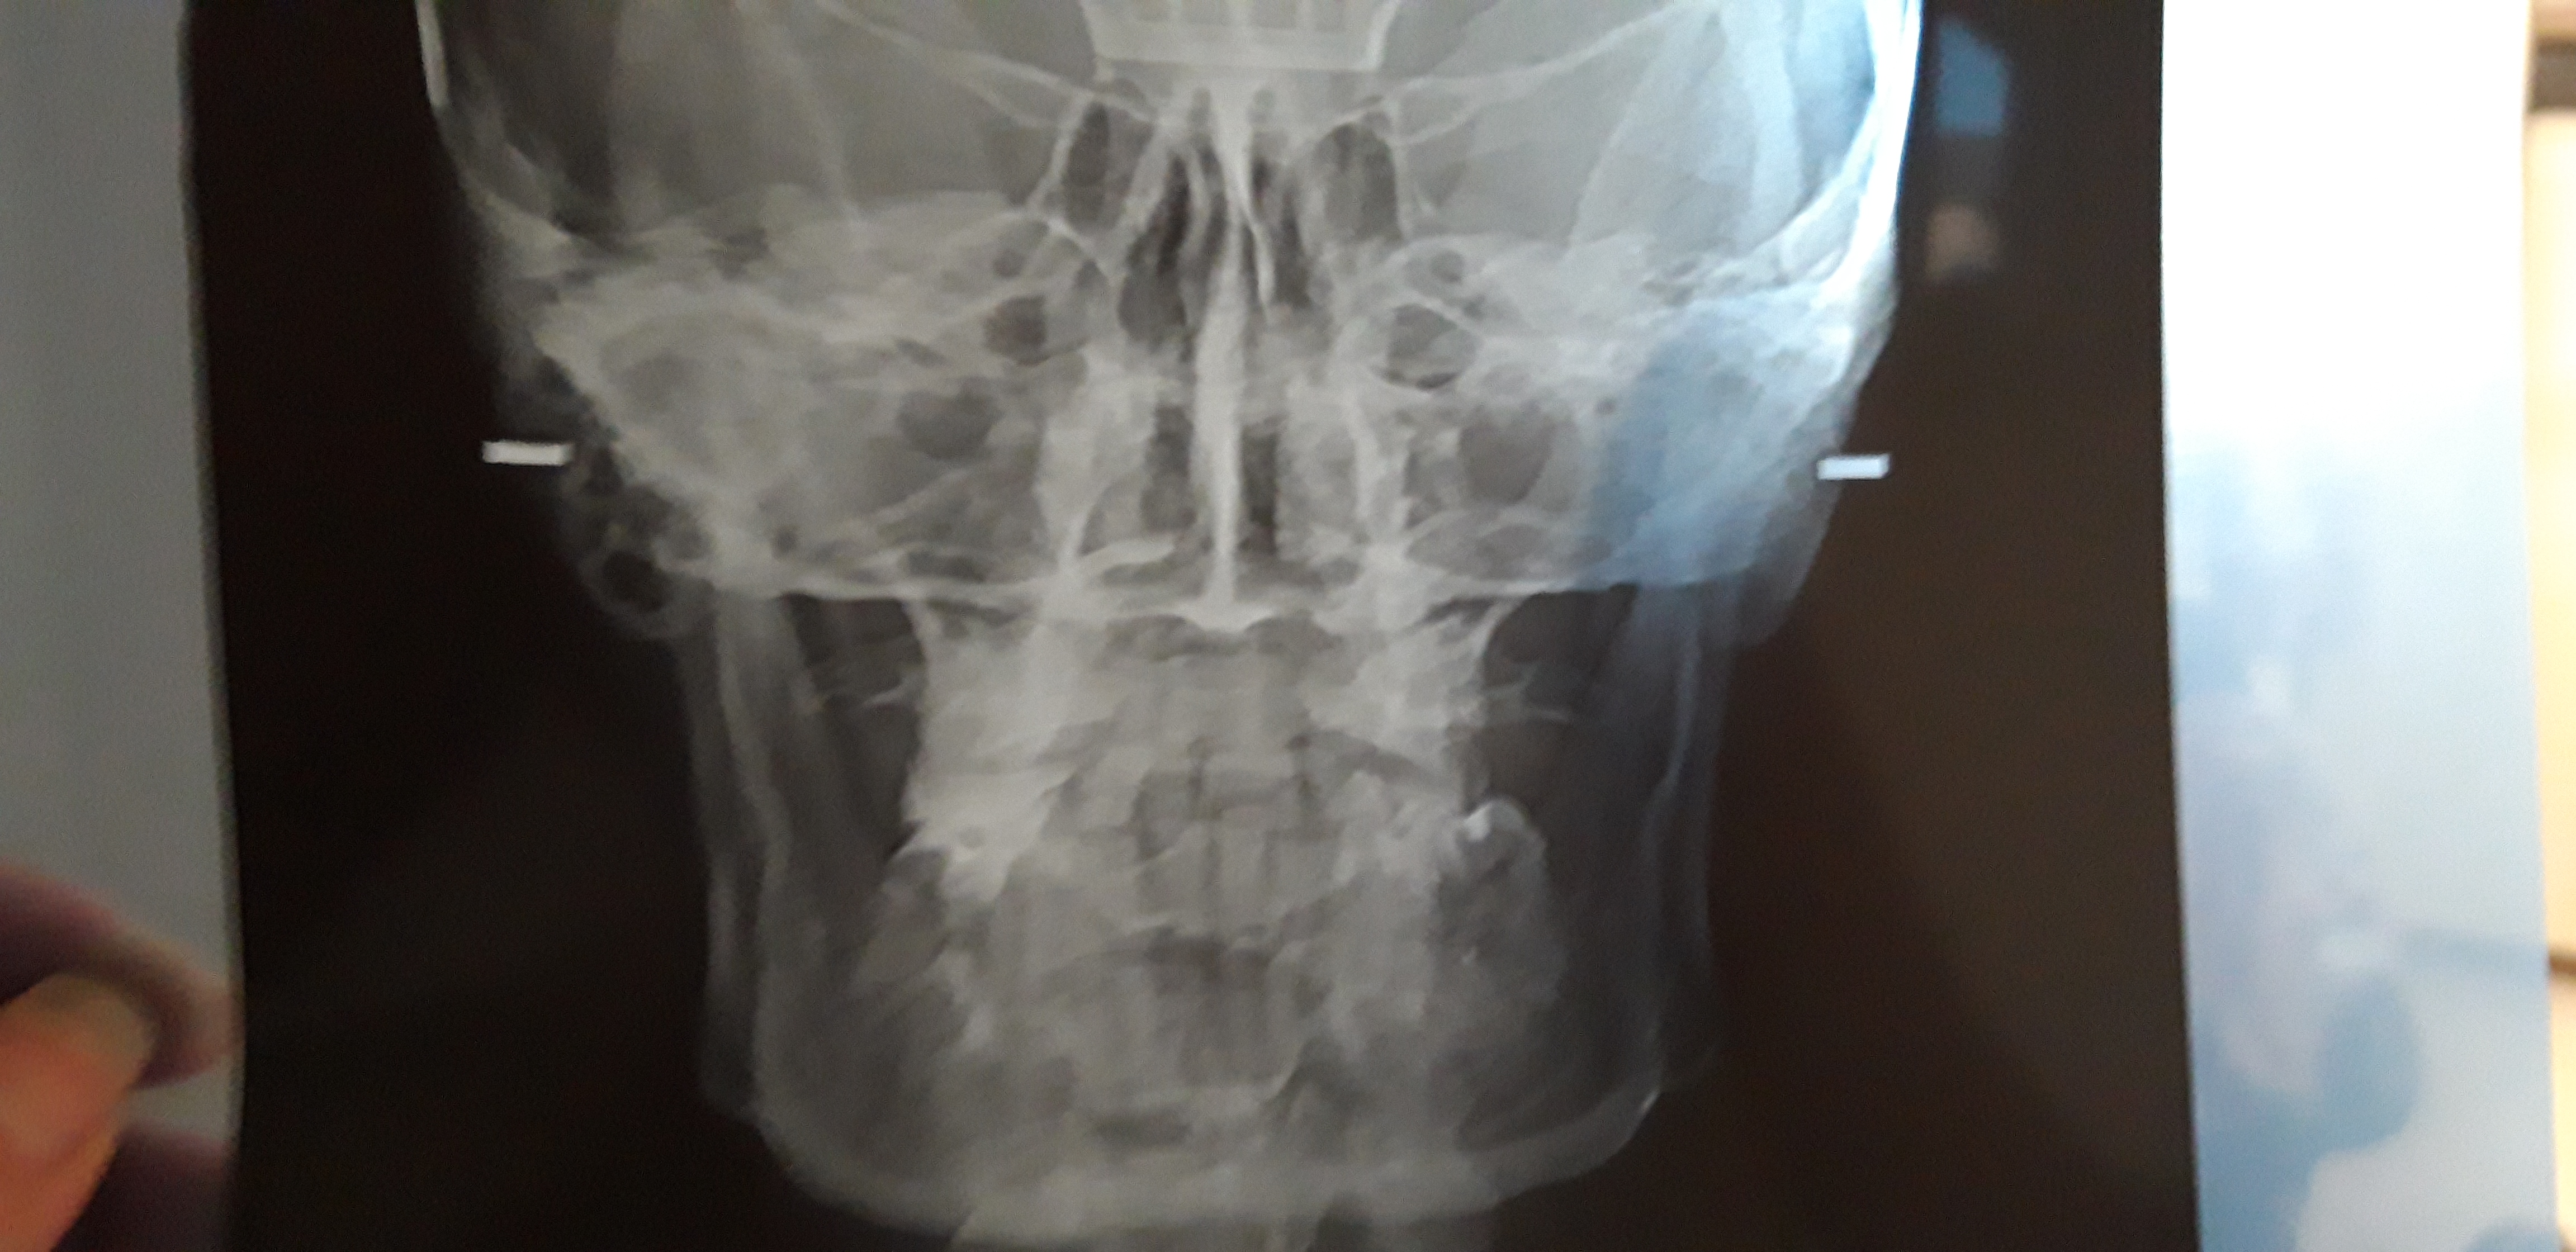

Commento file: Telecranio

20190612_190153.jpg

Buonasera sono due anni d ad oggi i sofferenza e pochi giorni fa ho trovato un Otorino il quale mi diceva che potevo essere affetta da tale sindrome in atessa di effettuare una Tac del massiccio facciale osso ioide .

Nel mentre allego il file di esame effettuato un po' di tempo fa in attesa di un parere o pinione . Grazie